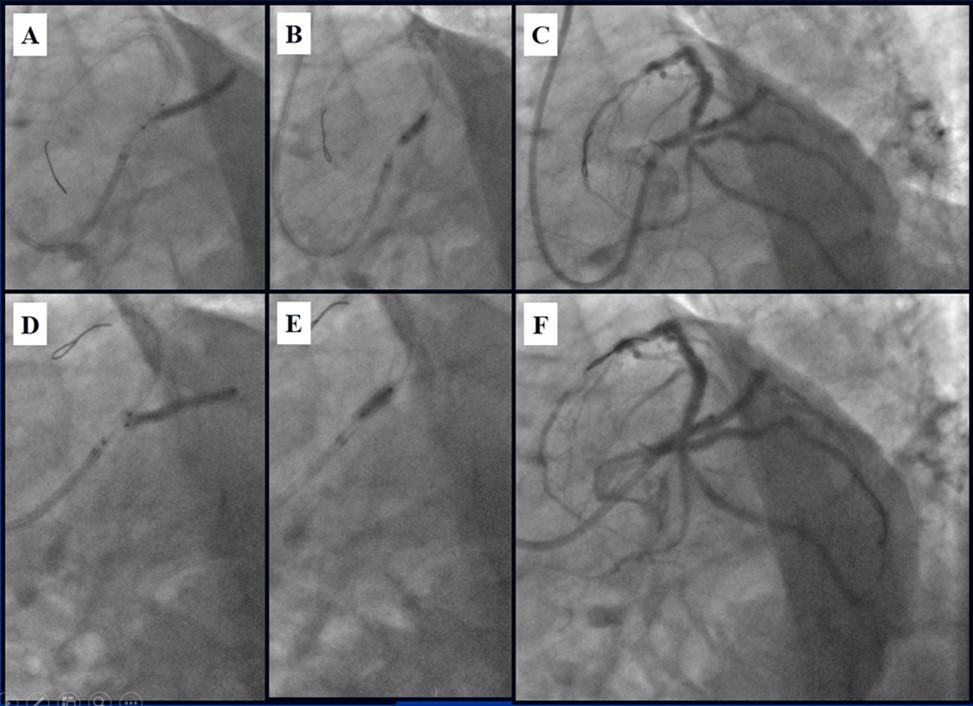

Due to financial problems the second stage was performed after 3 months (during this time the patient solved his financial problems). CAG revealed patent stents in LAD (Figure 7), and 60-70% restenosis by BMS in RCA (Figure 8). In-stent restenosis was treated by plain old balloon angioplasty (POBA), the optimal result was obtained (Figure 9). After LMCA quadrifurcation balloon predilation, 2.5×26 mm DES (Resolute Integrity, Medtronic) was implanted in the IMA, using a modified balloon mini-crush technique. The stent was minimally protruded in the LMCA and its edge was crushed by preloaded MB balloon. Next 2.5×30 mm DES (Resolute Integrity, Medtronic) was implanted in OM1 through the CX (first marginal and circumflex arteries in this particular case have the same ostium). The stent was protruded in the LMCA as in conventional modified balloon crush stenting technique, after stent deployment, its balloon was pulled back and overinflated, then protruded stent was crushed by preloaded MB balloon (Figure 10). 3.5×15 mm DES was implanted in the LMCA so that distal part of the stent covered ostial and proximal segments of the LAD. Sequential post-dilatations were performed using a kissing balloon technique (1. LMCA-LAD-IMA,2. LMCA-LAD-CX-1OM). After post-dilatations, through the stent implanted in CX-OM1, coronary wire and smaller diameter balloon (2.0 mm) were advanced in direction of the CX mid-segment and by balloon dilatation stent’s strut was opened (provisional stenting technique for CX). Finally, the proximal optimization technique was performed in the LMCA using a 3.5 mm diameter non-compliant balloon (Figure 11). The final angiographic image was good, the intervention ended without complications (Figure 11, Figure 12). We could not confirm the result with IVUS or OCT due to several technical and financial problems (not covered by insurance). 1 month after PCI, at regular checkout, the ejection fraction was 48%, the functional class of the Congestive Heart Failure decreased from class II-III to class I and the patient complaints have been disappeared.

Figure 10.Stenting of the LMCA quadrifurcation: A, B - balloon modified mini crush stenting of the IMA, C - angiography result, D,E - modified balloon crush stenting of the CX-OM1, F - angiography result.

Stenting of the LMCA quadrifurcation: A, B - balloon modified mini crush stenting of the IMA, C - angiography result, D,E - modified balloon crush stenting of the CX-OM1, F - angiography result.